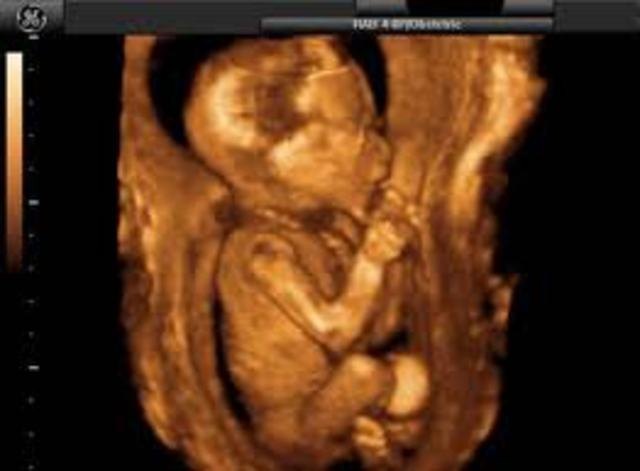

Pregnancy and Prenatal Development

month 4 baby and mommy the baby is about one inch can suck its thumb the mommyadomen continues to grow slowly morning sick ness is gone appitite is gone